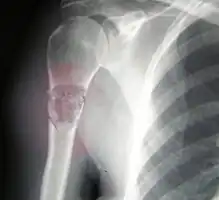

-

Osteosarcoma of the distal femur -

Metastatic osteosarcoma to the left chest -

Telangiectactic osteosarcoma of the humerus

Mechanism